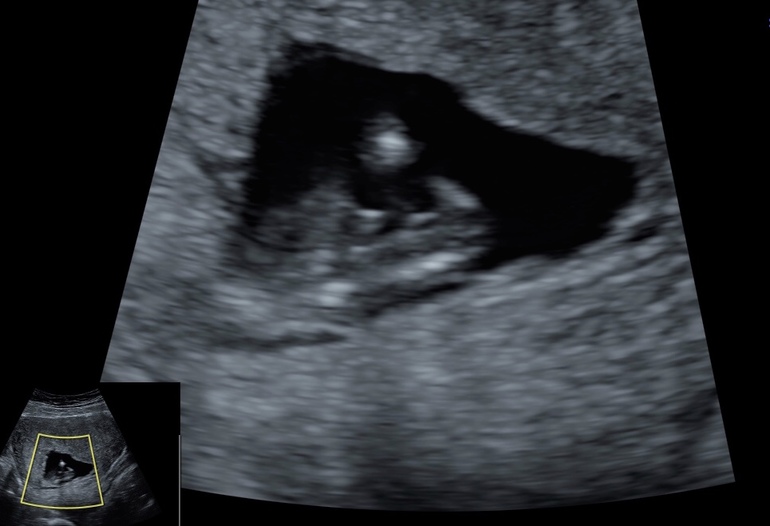

Пол малышаДевочки, давайте погадаем! Последнее УЗИ было на сроке 11,4 недель, но врач не рискнула предположить, сказала рановато! Я не совсем в этом разбираюсь, видно ли тут половой бугорок или нет, может кто-то понимает?

Ну вот вы видели фотографии 4д на таком сроке, я сначала подумала почему голова не ровная? А точно это нормально? )) и чтобы люди не заостряли внимание на этом, я закрыла голову))) но как оказалось, людям все равно на чем заострять внимание))) а мне вот интересно, неужели вам так не все равно что делает с фото своего ребёнка его мать? Может я так сильно боюсь всего и боюсь сглаза? А может это просто мой беременный загон? Вам не все равно? Вопрос ведь был совсем о другом!